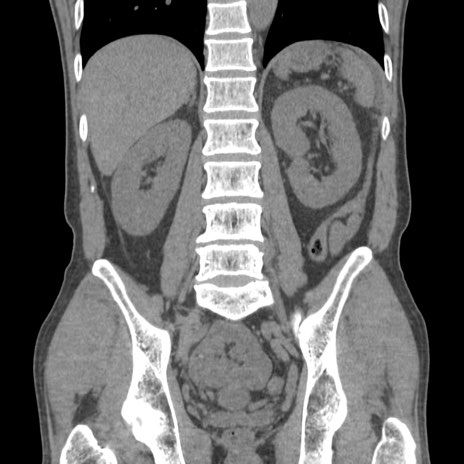

症例56 CT(冠状断像)

横断像